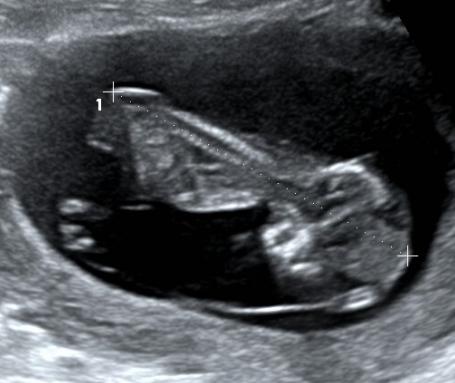

3个月,也就是约12周。

此时胎动已经开始活跃了,只是孕妈妈可能还感受不到。但在超声下却可以看到TA很活泼哟。

除了心跳,我们还能看见TA的整个身体雏形了。

手手脚脚都能看到一些。

甚至有时还能看见TA在肚子里舞蹈。

上图就是一个两脚朝天,此时我们可以在这个切面观察TA 的股骨长,股骨长的测值也可以作为矫正孕周的一个重要参数。